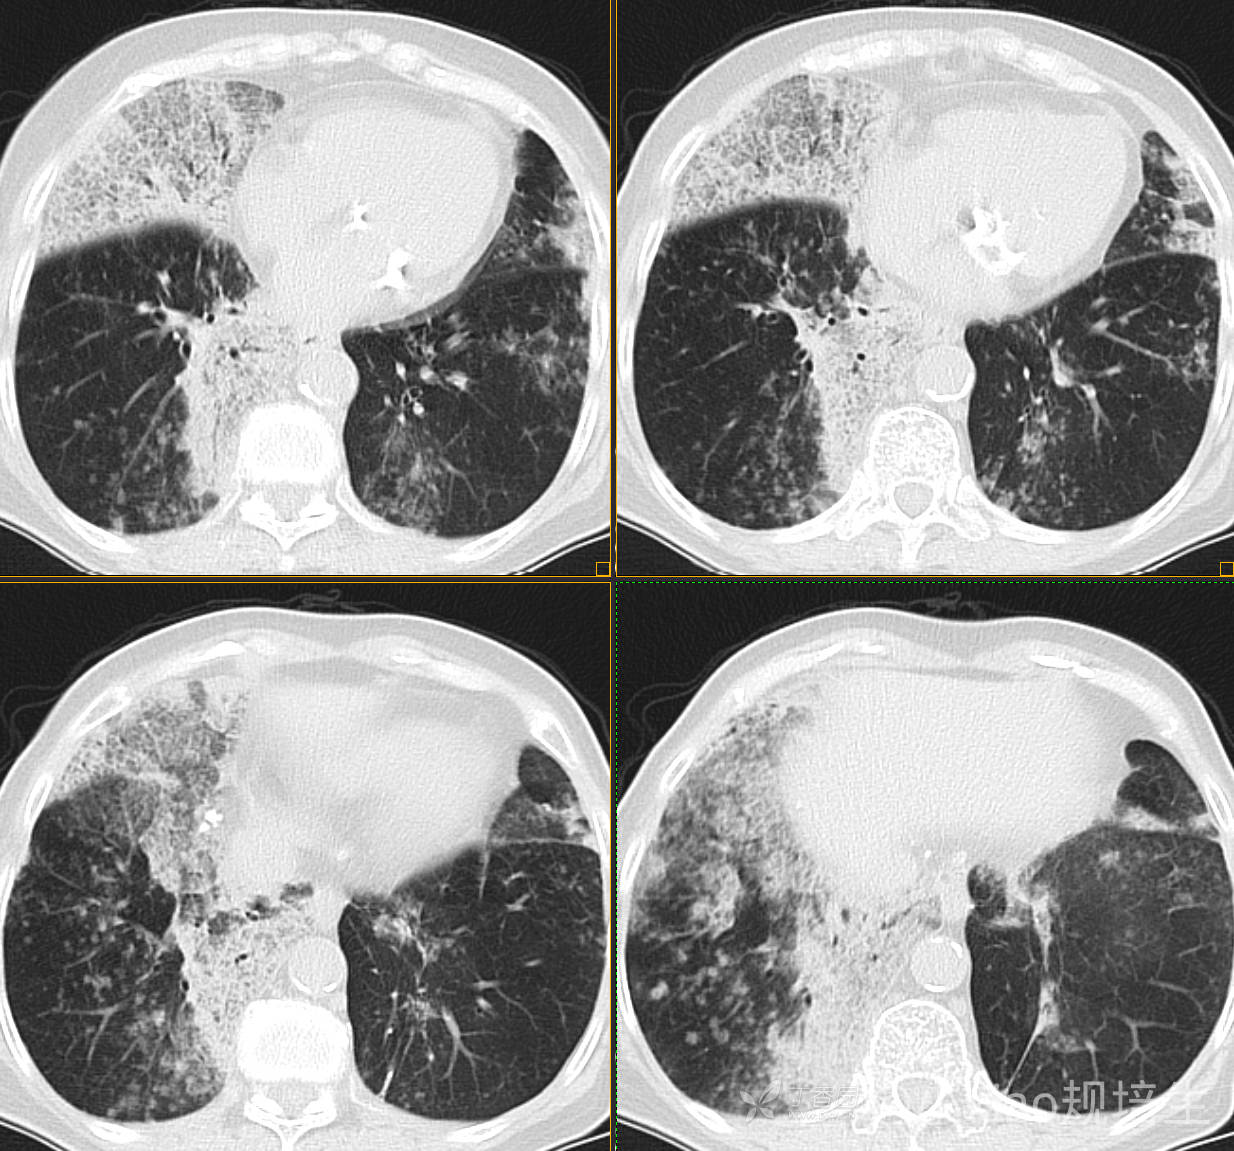

患者,女,89岁

咳嗽,咳痰一月余

肺泡蛋白沉着病 (19)

腺癌 (183)

弥漫性囊性肺病 (9)